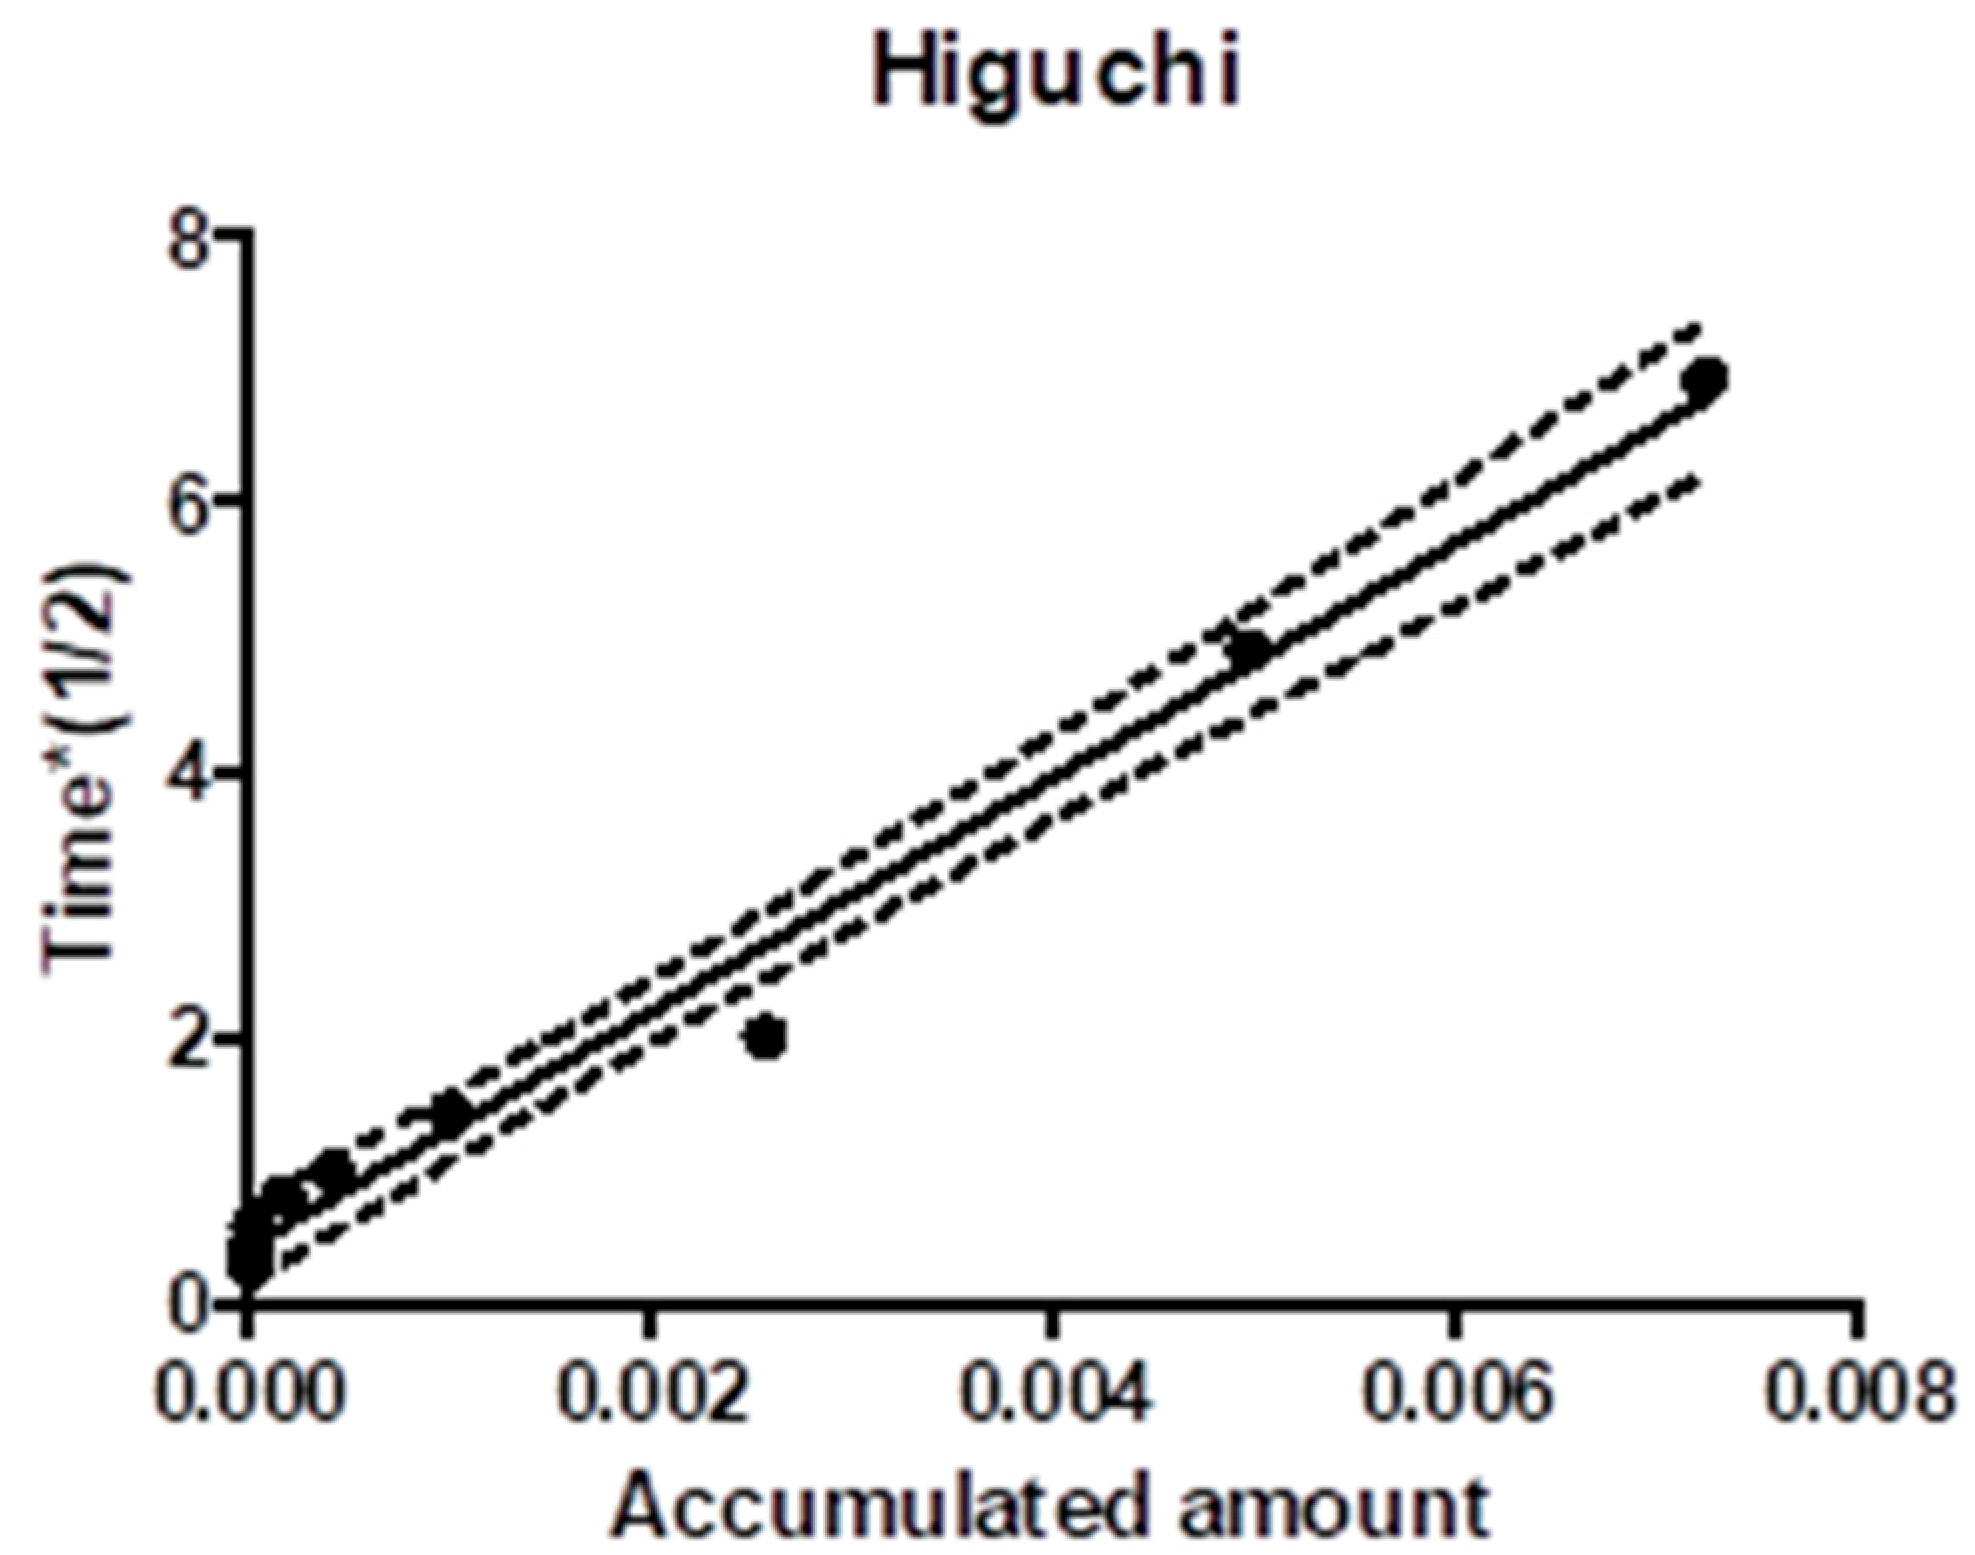

3.1.6. Drug Release Profiles and Kinetic Drug Release